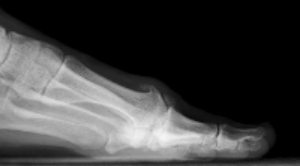

X-rays are commonly used to confirm the diagnosis and may show joint space narrowing, bone spurs, and degenerative changes of the MTP joint. Advanced imaging is rarely required but may be considered in select cases to evaluate associated cartilage damage or prior injury.